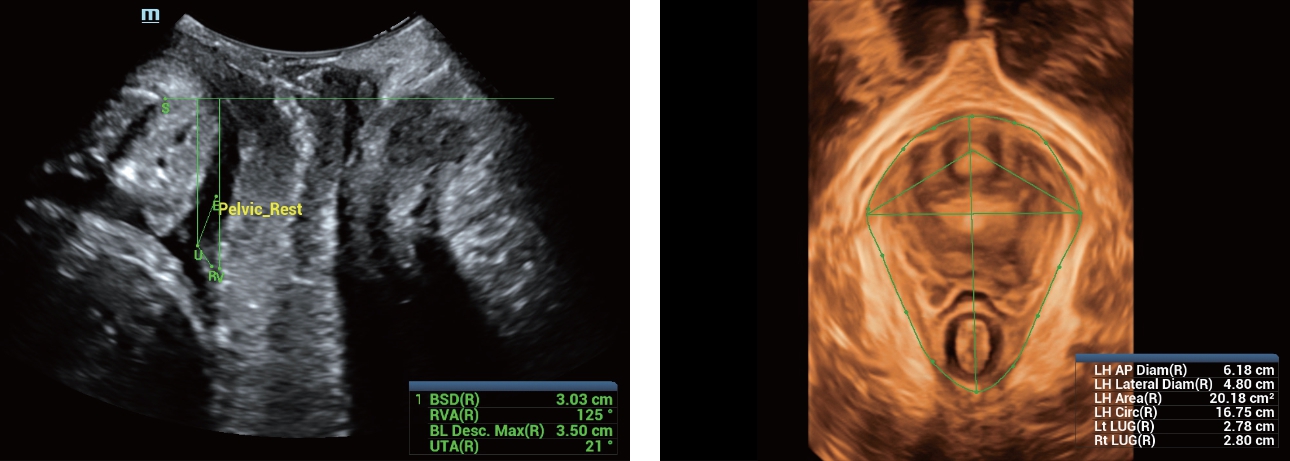

Selain kualitas gambar premium, Resona 7 juga meningkatkan kemampuan penelitian klinis dengan V Flow revolusioner untuk evaluasi hemodinamika vaskular, serta pengambilan penampang tercanggih dari rangkaian data 3D untuk diagnosis CNS pada janin. Kombinasi pengoperasian multisentuh berbasis gerakan yang paling intuitif dengan semua fitur klinis penting membuat Resona 7 menjadi gebrakan baru dalam inovasi ultrasound.